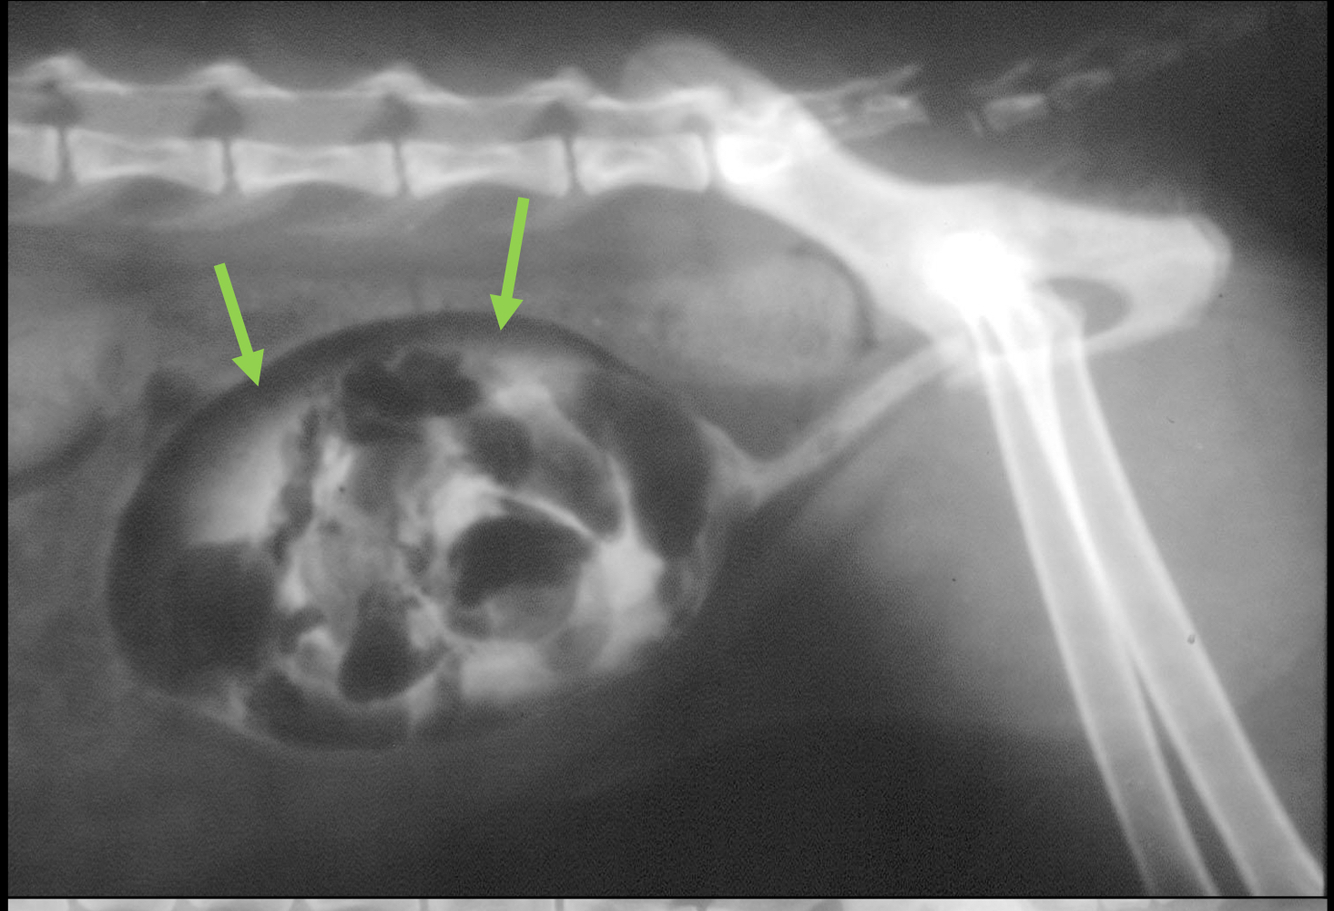

What is being pointed to in this cystourethrograph?

A

filling defects where contrast is not taken up